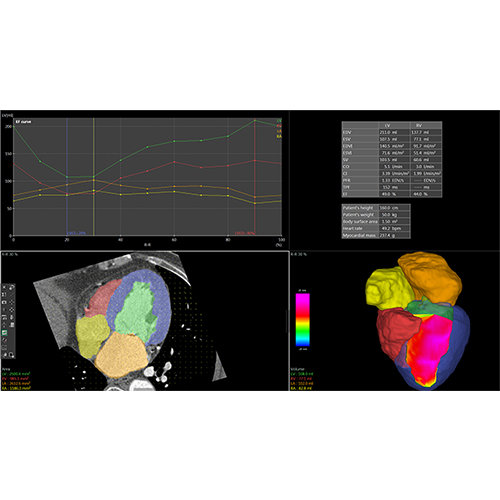

ANYTHINK 经导管主动脉瓣膜置换术分析系统